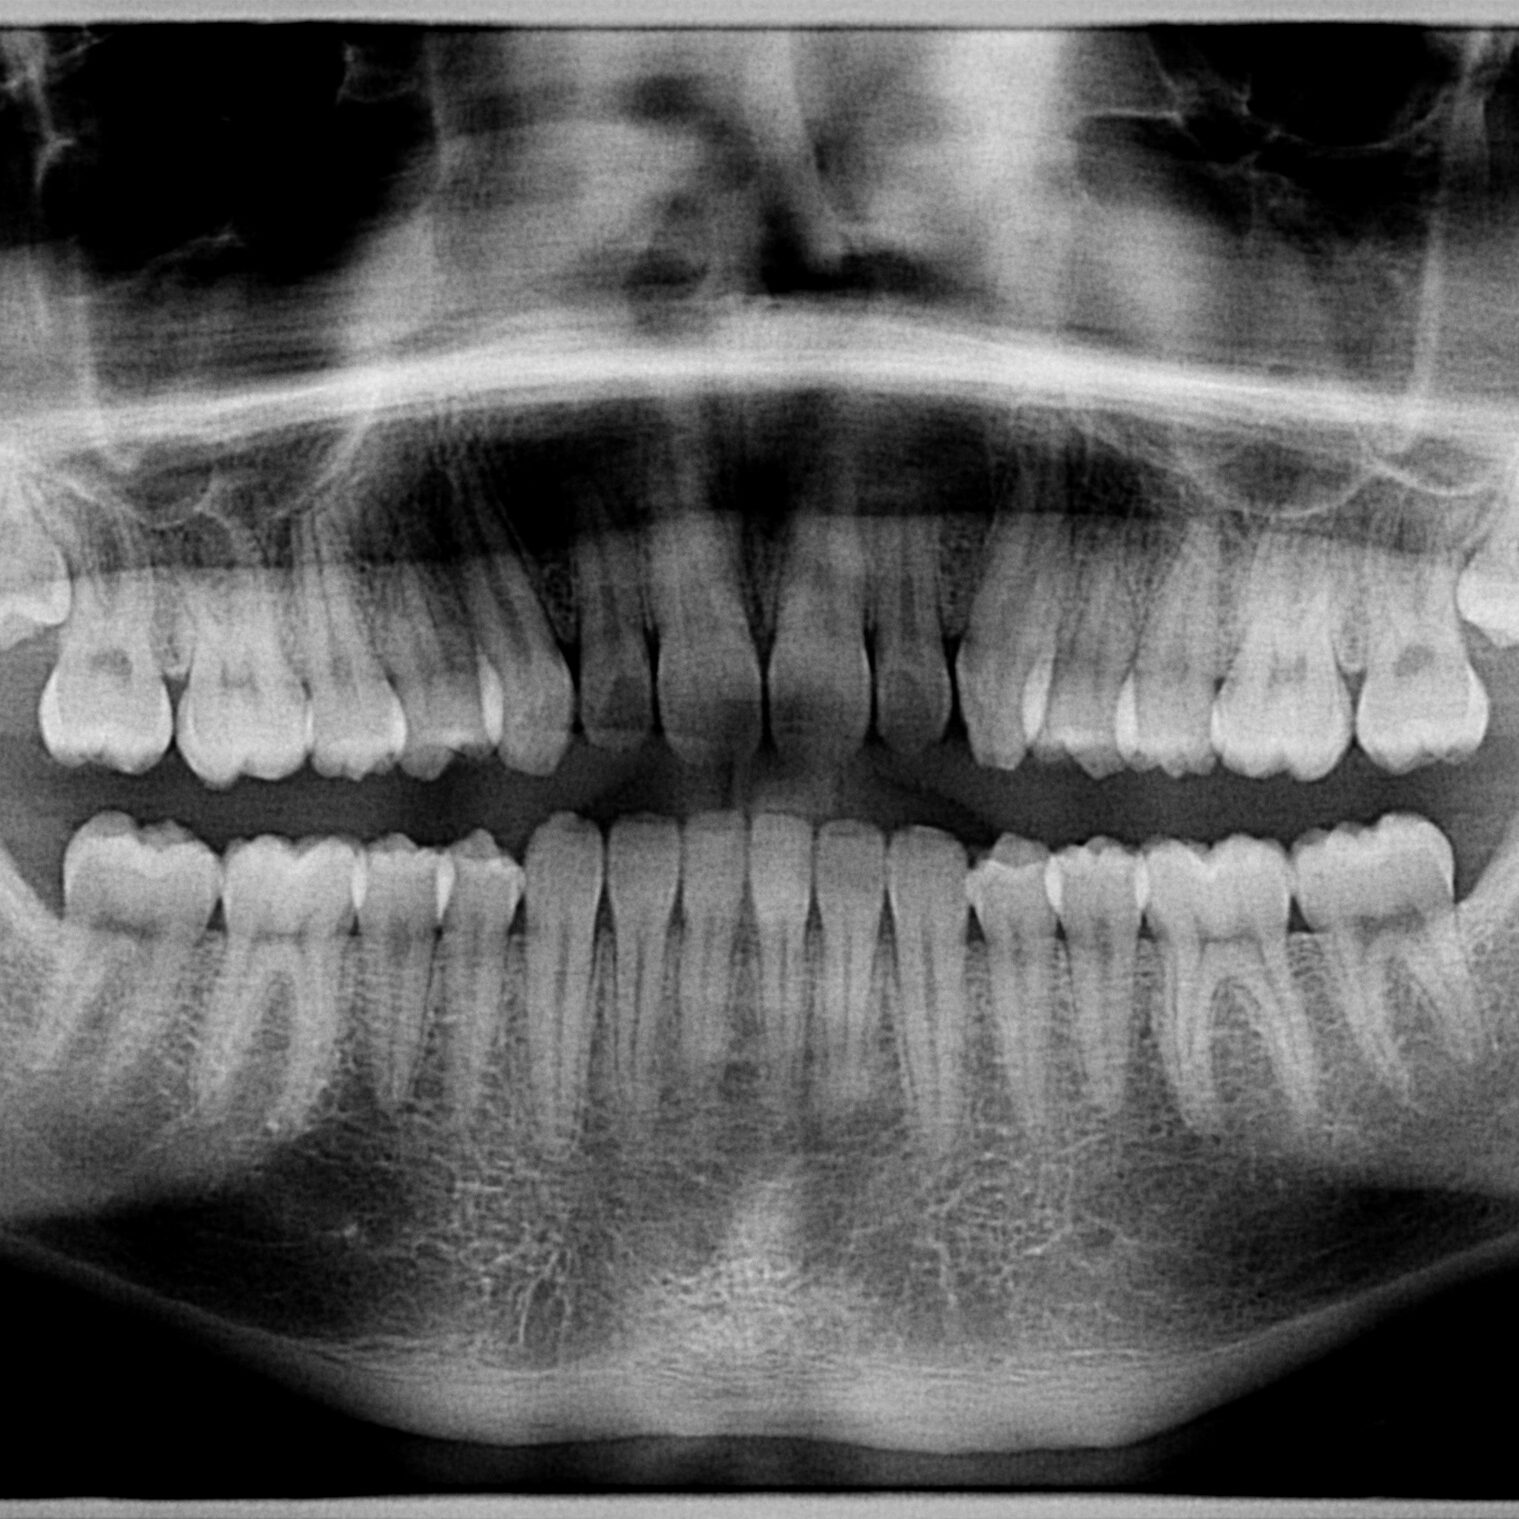

Orthopantomogram

X-ray panoramic two-dimensional image of the jaw that enables quick and easy diagnosis of almost all dental problems.

In addition to the classic orthopantomogram, a bitewing scan and scans of the maxillary sinuses and temporomandibular joint are also available.